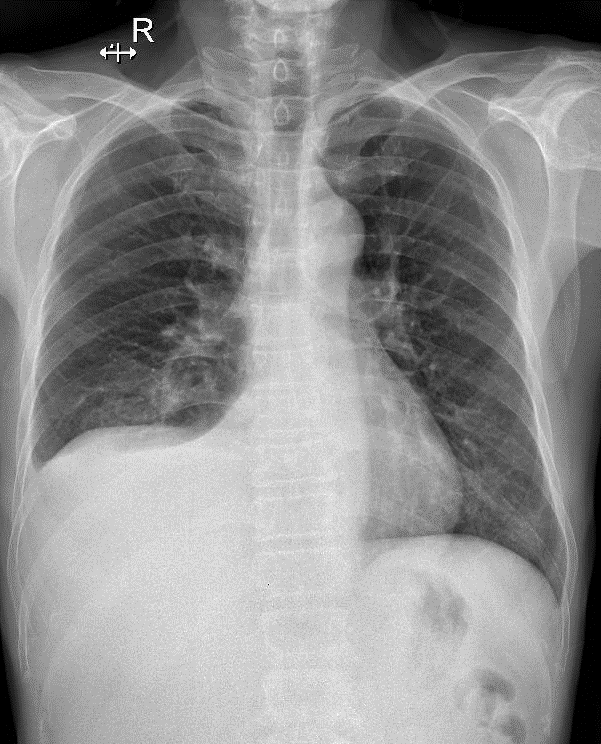

-Thâm nhiểm phế nang thùy dưới phổi (P) => Viêm phổi -Tràn dịch màng phổi (P) lượng ít